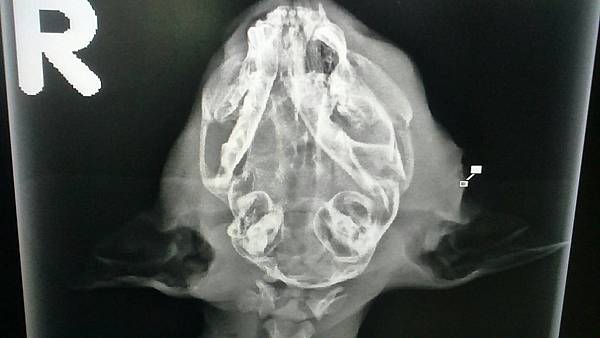

被狗狗咬到頭部,牙齒咬破了頭骨

另一側也有凹洞

頭部X光

這孩子因為被狗咬傷,頭骨多處破裂粉碎

腦血腫腦壓過高,一直呈現低頭狀態